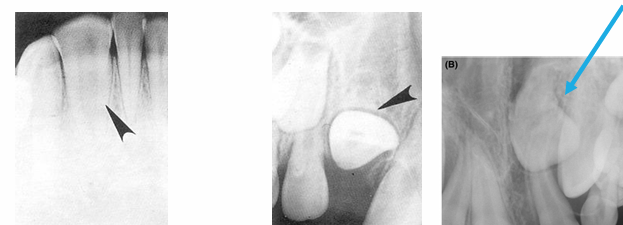

-anomalies (supernumerary, missing permanent teeth, mesiodents)

trauma

-soft tissue radiograph

-indicated after trauma to locate piece(s) of fractured tooth